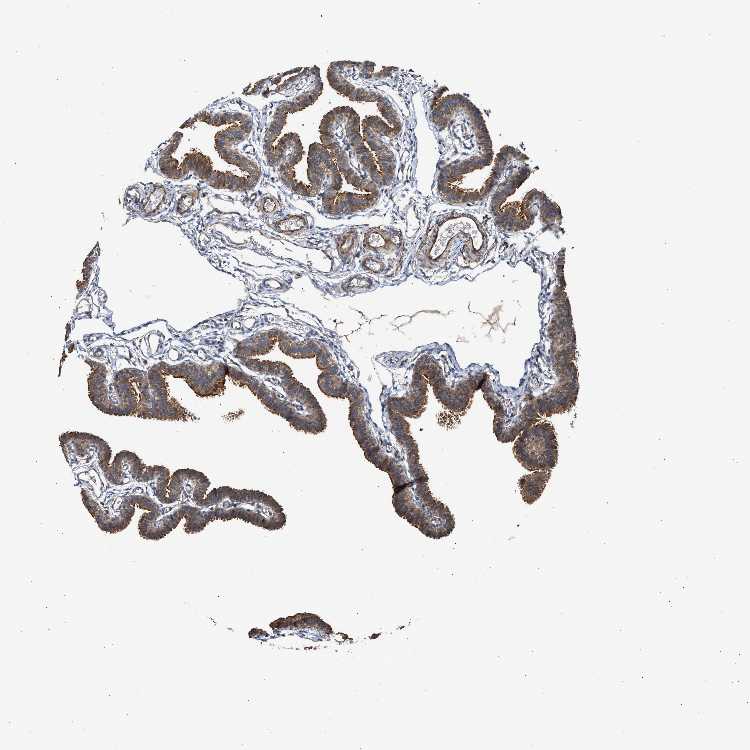

FALLOPIAN TUBE - Antibody stainingi

Antibody staining in the annotated cell types in the current human tissue is reported as not detected, low, medium, or high, based on conventional immunohistochemistry profiling in selected tissues. This score is based on the combination of the staining intensity and fraction of stained cells.

Each image is clickable and will lead to virtual microscopy that enables deeper exploration of all samples and also displays staining intensity scores, fraction scores and subcellular localization as well as patient and tissue information for each sample.

Antibody CAB020716

Glandular cells High